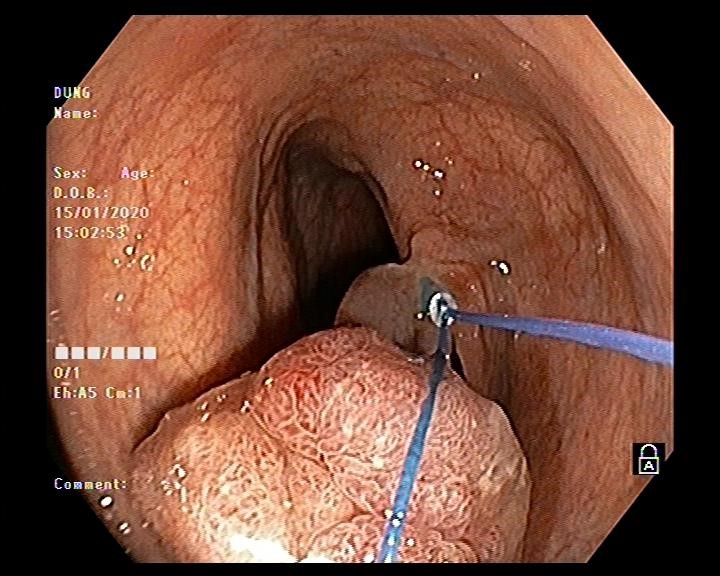

Hình ảnh thắt cuống polyp bằng vòng Endoloop

Vấn đề đặt ra là với kích thước và tính chất polyp như vậy thì có khả năng polyp được nuôi bằng mạch máu lớn, nếu chỉ cắt đốt bằng phương pháp thông thường thì nguy cơ xuất huyết ồ ạt sẽ rất cao. Do đó bác sĩ nội soi Ths Vũ Thanh Tùng quyết định sử dụng vòng Endoloop để thắt cuống polyp trước khi tiến hành cắt đốt. Thủ thuật diễn ra thuận lợi, nhanh gọn trong vòng 10-15 phút và không xảy ra tai biến dù là polyp này được nuôi bằng mạch máu lớn.

Kỹ thuật sử dụng vòng Endoloop để thắt cuống polyp lớn là một kỹ thuật được áp dụng tại Đơn vị nội soi Bệnh viện đa khoa tỉnh Hải Dương từ tháng 10 năm 2019. Với những tiến bộ trong các công cụ hỗ trợ nội soi hiện nay như Endoclips và Endoloops, nó đã trở nên an toàn hơn để thực hiện kỹ thuật nội soi cắt polyp cuống lớn. Cấu tạo của Endoloop gồm 2 phần: phần cán của Endoloop có cấu tạo gần giống như cán của thòng lọng, có bộ phận để đưa vòng Endoloop vào chân polyp, phần thứ 2 là vòng thắt được cấu tạo bằng chất dẻo đặc biệt có gắn thêm ống nhựa như một một cái khóa vòng thắt. Để ngăn ngừa chảy máu sử dụng dụng cụ Endoloop như một dây ga rô buộc chặt cuống polyp ở vị trí sát chân polyp trước khi tiến hành cắt bằng thòng lọng. Sau khi cắt polyp dụng cụ Endoloop vẫn còn lại vài ngày sau ở phần chân polyp cho đến khi phần này teo lại dụng vào lòng đại trực tràng.